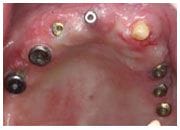

植牙過程

植入植體